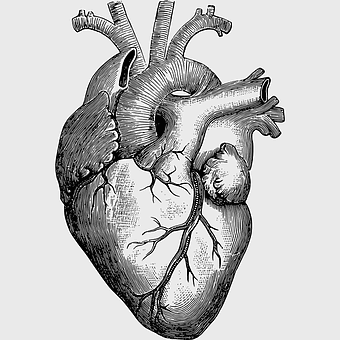

human heart diagram, monochrome anatomy drawing, black and white heart illustration, human organ sketch, cardiovascular system diagram, medical illustration heart, heart structure outline -

human heart anatomy, cardiovascular system illustration, medical heart diagram, heart organ structure, human body organ visuals, anatomical heart drawing, heart health -

human heart diagram, cardiovascular system anatomy, blood vessel chart, free body diagram, circulatory system illustration, medical organ visualization, human anatomy study -

human heart anatomy, cardiac muscle illustration, circulatory system model, heart health visual, cardiovascular organ diagram, medical heart image, visceral structure depiction -

heart anatomy diagram, human heart ventricle, human body physiology, heart beat animation, cardiovascular system, medical illustration, organ structure analysis -

human heart anatomy, heart science illustration, human body heart diagram, cardiovascular system, cardiac structure, medical heart image, heart health education -

heart sketch, human heart anatomy, monochrome organ drawing, patricia visser art, cardiovascular system illustration, medical biology diagram, black and white anatomy chart -

heart anatomy diagram, circulatory system illustration, superior vena cava label, inferior vena cava structure, cardiovascular system chart, human heart ventricles, medical education graphics -